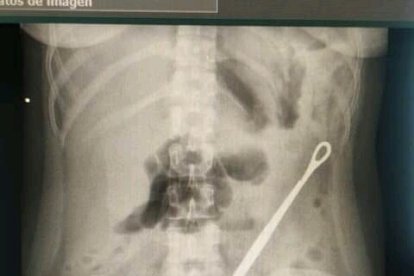

Por fin, se decidieron por una radiografía de la espalda. Con el resultado, la joven se dio cuenta qué le estuvo pinchando el pulmón izquierdo: era la pinza de puntas redondas y de aproximadamente 16 centímetros. “No lo creía. Sentía miedo de lo que me podía ocurrir”.